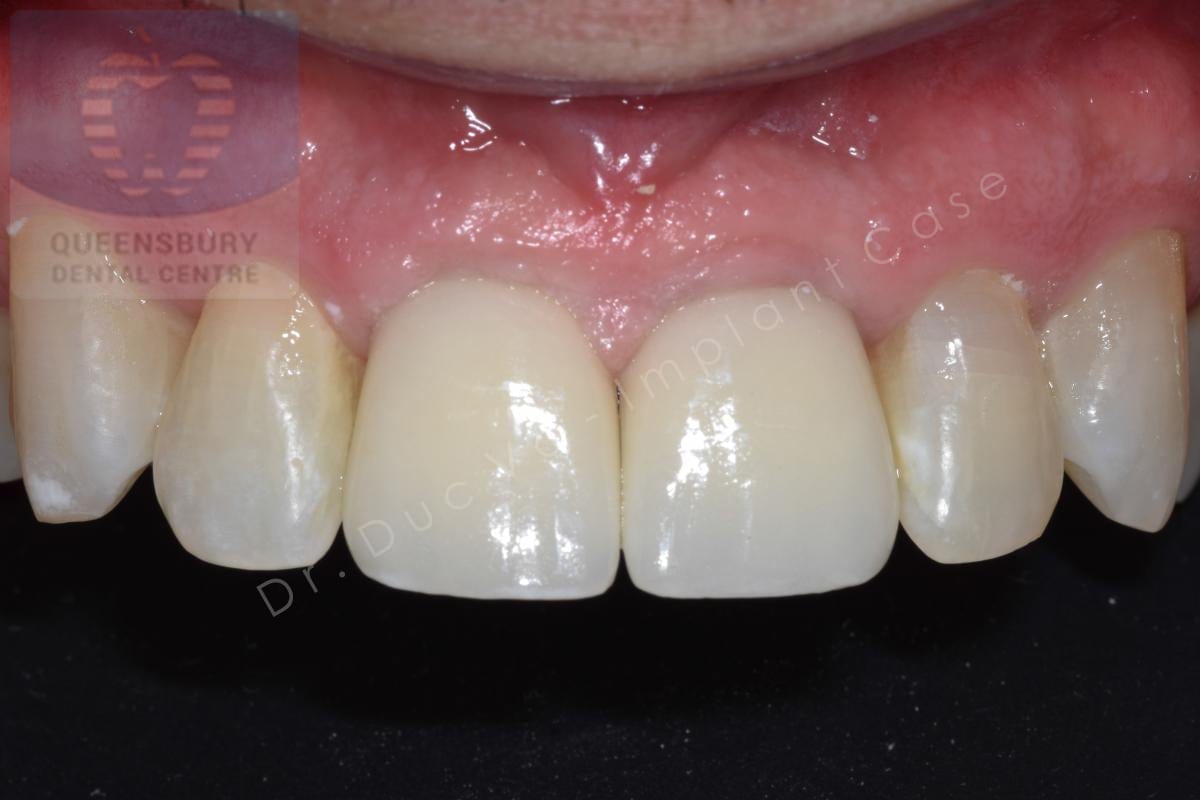

Missing teeth and loose dentures make many people avoid social settings because they are too self-conscious about their appearance. Current dental procedures, however, replace everything from a single missing tooth to a completely missing arch. Ask your dentist or dental specialist about the different dental options that are available to you. Don’t let another day go by without taking this important first step to restoring your confidence and your smile!